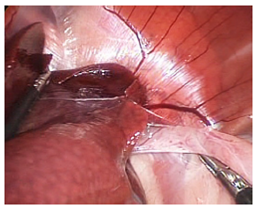

Six New Zealand rabbits (Oryctolagus cuniculus), between 2.5 and 3.5 kg of weight were used. Animals were laid supine with a 15° anti-Trendelenburg position, and access ports were established. A first port was placed in the midline, between the last two pairs of mammary glands, where a 10 mm trocar for the lens was introduced by blunt dissection (Hasson technique). A 0° telescope was used. The abdomen was insufflated through this port reaching a 10mmHg pressure. Once intra-abdominal vision was achieved, three additional 3 mm ports were established, one slightly cranial to the right and two slightly cranial to the left of the telescope (Fig. 1). The stomach, hiatal region and esophagus were identified. Conventional surgical instruments, such as Maryland forceps, needle holders and scissors, were used for the procedures. The surgeon utilized the two 3 mm ports located immediately adjacent to the telescope. In addition to handling the lens, the surgical assistant helped the surgeon with the esophagus dissection by using the farthest port from the left side, in order to restrain the stomach with forceps at the antrum. The stomach was pinched with forceps at the antrum to create traction. The esophagus was then dissected and separated from the diaphragmatic cruras. Care was taken to preserve the vagus nerves. The gastric fundus was subsequently passed behind the esophagus, and a 360º “floppy” Nissen fundoplication fixed with three surgical knots was performed using a 3-0 poliglactin 910 suture. All animals were euthanized after surgery completion, and digestive tract patency and presence of leaks were assessed. Next, surgically concerned organs were resected for histopathological examination (Fig. 2).